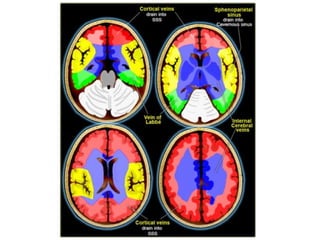

f) Cerebral Venous Territory :

-There is great variation in the territories of